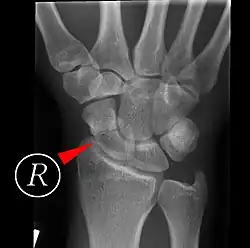

Scaphoid fractures may be difficult to diagnose via plain x-ray. A repeat x-ray may be required at a later date, as might cross-sectional imaging via MRI or CT scan.[6]

A condition called scapholunate instability can occur when the scapholunate ligament (connecting the scaphoid to the lunate bone) and other surrounding ligaments are disrupted. In this state, the distance between the scaphoid and lunate bones is increased.[1]: 180